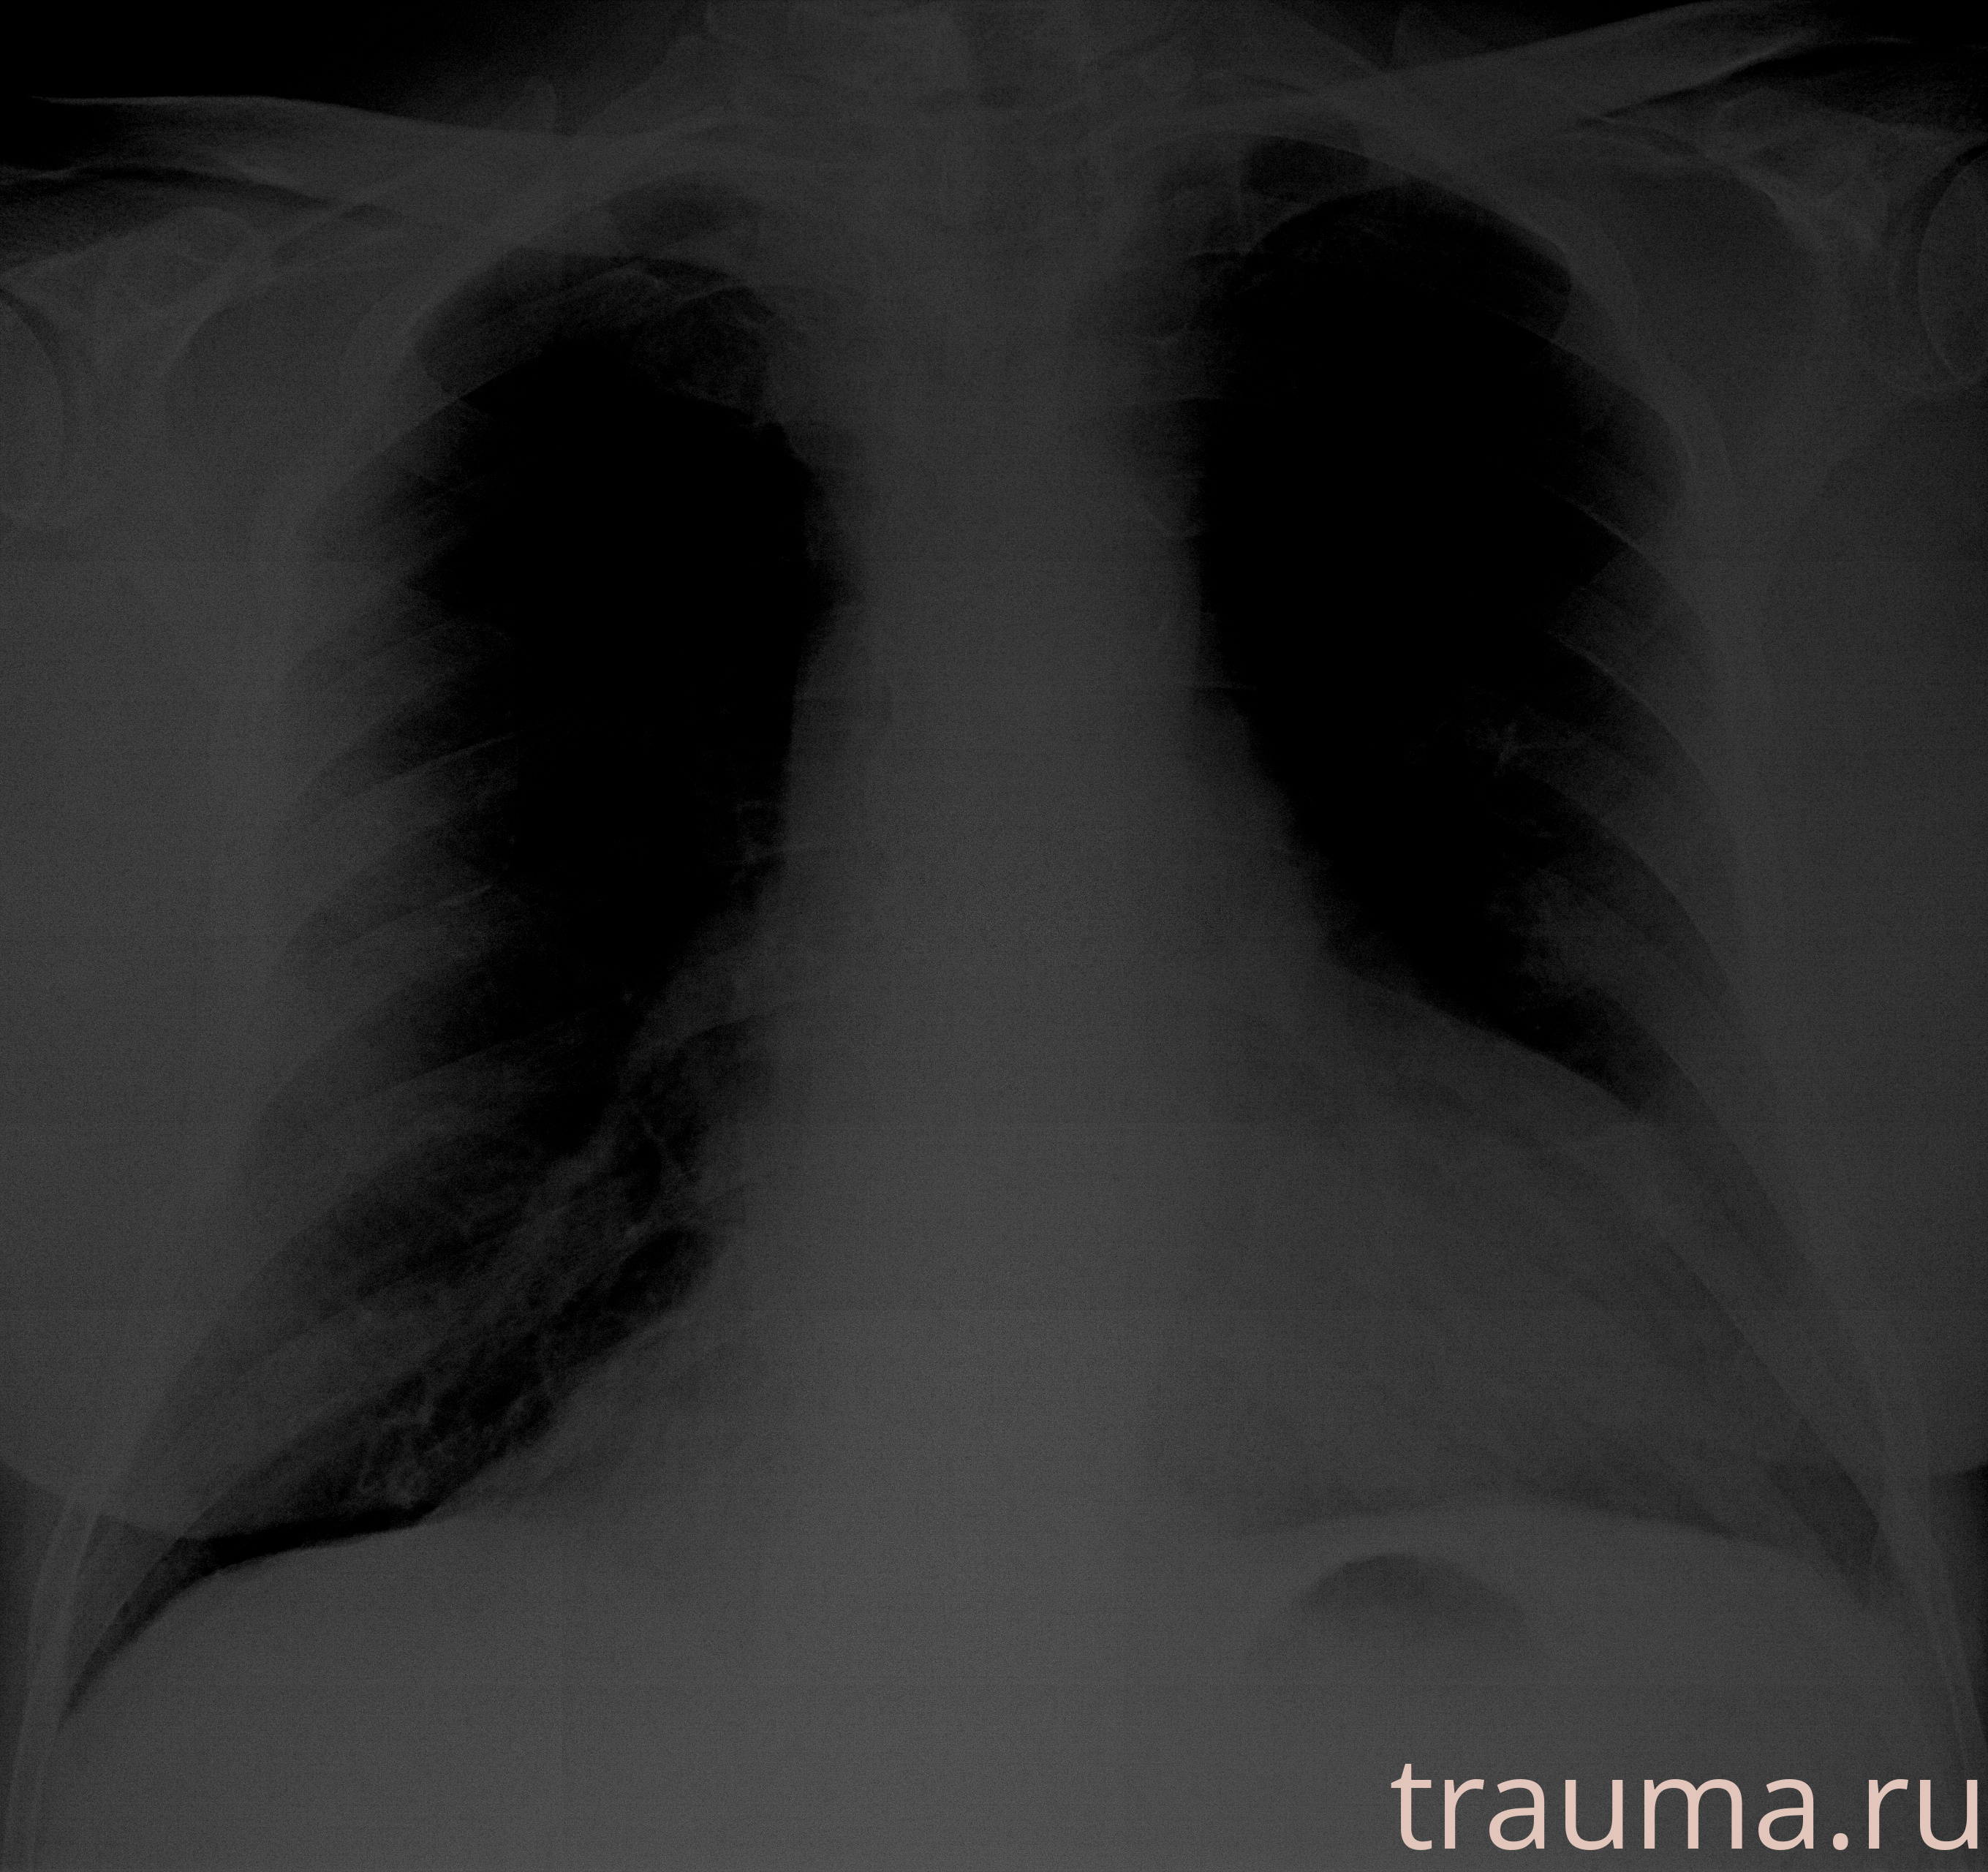

Рентгенограммы

Рентген на дому: по вашему адресу приезжает врач-рентгенолог, травматолог-ортопед с мобильным рентгеновским аппаратом, проводит диагностику травмы или заболевания, делает необходимые рентгенограммы, дает рекомендации по дальнейшему лечению. Получить качественные снимки в домашних условиях возможно благодаря уникальной методике, разработанной МосРентген Центром для института  Склифосовского

при переломе шейки бедра и пневмонии от компании МосРентген Центр - партнера Института имени Склифосовского